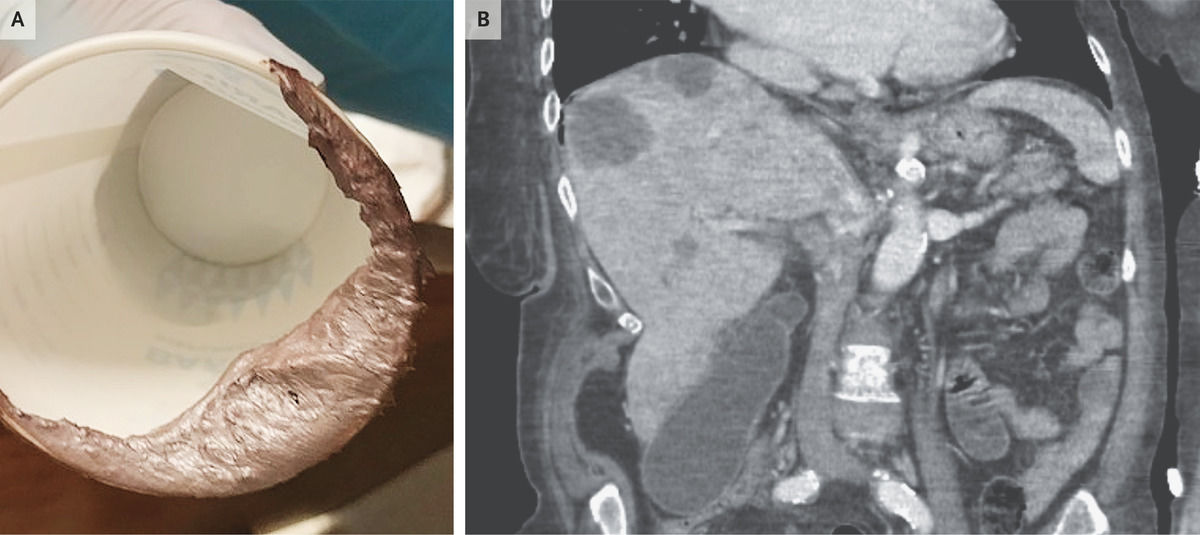

البراز الفضي #البراز_الفضي (علامة #توماس): مرض السرطان #السرطان #أمبولة_فاتر. كانت هذه الحالة #السرطان_القولون_المنتشر.

ما الذي يسبب لون #البراز_الفضي؟

يمكن أن يحدث البراز ذو اللون الفاتح (رمادي أو بلون الطين) عند البالغين بسبب نقص #الصفراء في الجهاز الهضمي. عادة ما يكون من انسداد في القنوات الصفراوية ، إما من حصوة أو ورم. تساعد الصفراء على هضم الدهون وهي مسؤولة عن اللون البني للبراز.